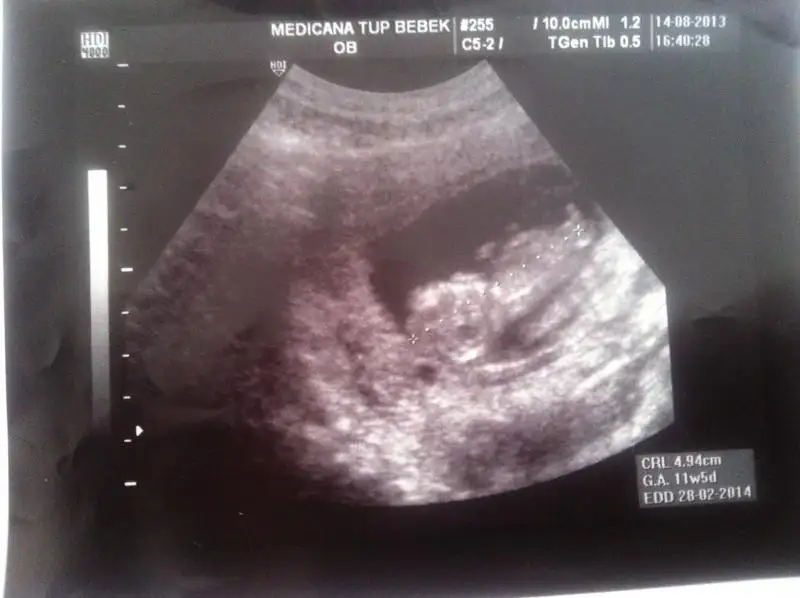

buda benim bebeğimin ultrason görüntüsü

henüz 11 +3 haftalık resmine çıplak gözle bakınca popo kısmında bir çıkıntı görülüyor fakat resmi tarayıp yükledim ama pek bir şey anlaşılmıyor galiba

acaca görebildiğiniz kadar yorum yapabilir misiniz Eki Görüntüle 806765 Eki Görüntüle 806765

Dikkatli baktım canım sanin çıkıntın paralel KIZ .. Gönlündeki olsun